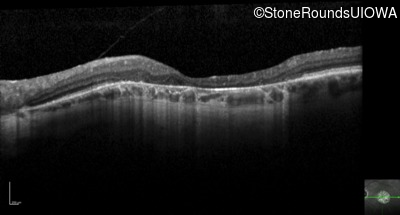

Optical Coherence Tomography - Left - 20/125 -1

Exemplar / OCT Stack